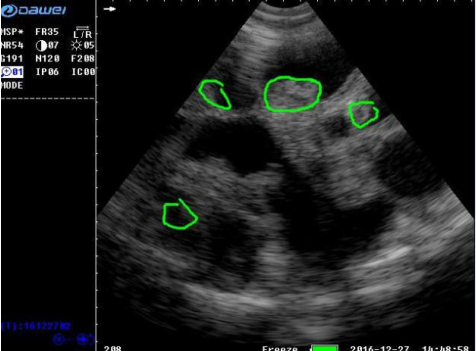

獸用b超機怎么看懷了幾個崽?